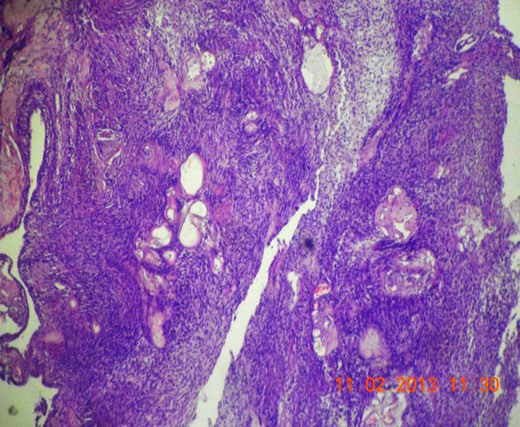

Gross appearance showed 6 × 4 × 4 cm smooth encapsulated right thyroid swelling with a posterior cystic area which was yellowish brown in colour. Walls of the cyst were bright yellow with polypoid areas (Fig. 4). Histology showed classical Antoni A (hypercellular areas) with Verocay bodies and Antoni B (hypocellular) pattern, with interspersed thyroid cells along the periphery (Figs 5–7). The lesion was reported to be arising from within the thyroid gland itself and not extrinsic to it.

Microscopic section (H&E slide, 100×) of magnified view of a region in Fig. 6 showing Verocay bodies.